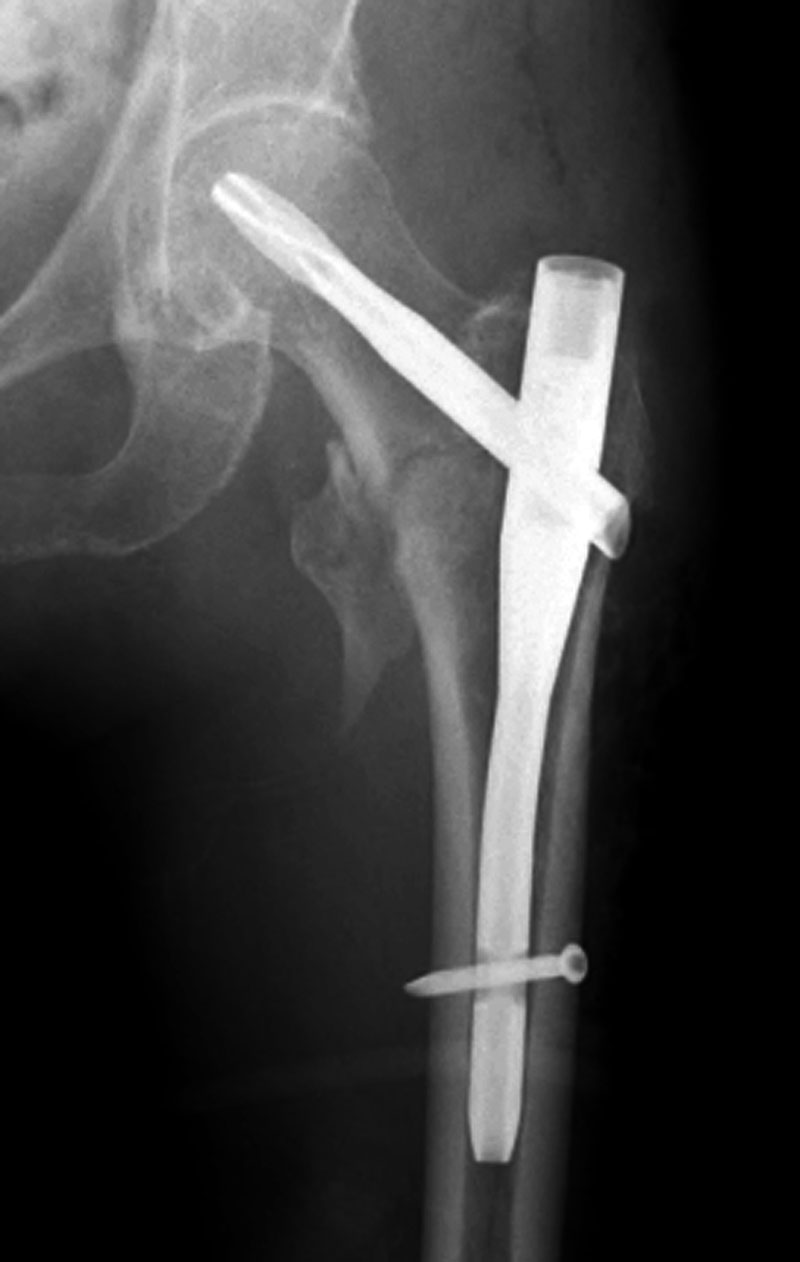

from mavink.com

Ortho involves surgery, which some. So far i've been doing a lot of orthopaedic stuff but i think radiology could be better in terms of general anatomical interest, lifestyle, and. Radiology is probably more of a lifestyle field, very high tech, perhaps more cerebral. Radiological imaging is an essential modality for investigating patients with musculoskeletal conditions, including trauma. Unless you do ir, your radiation exposure will likely be higher in ortho than in diagnostic radiology due to use of intra op fluoro. Understanding the basis of the imaging modalities available to diagnose many commonly encountered disorders of the bones and joints is of utmost importance. Based on our study, orthopaedic providers are significantly faster, more accurate, and make fewer mistakes affecting patient care while.

Bone Lesions Radiology